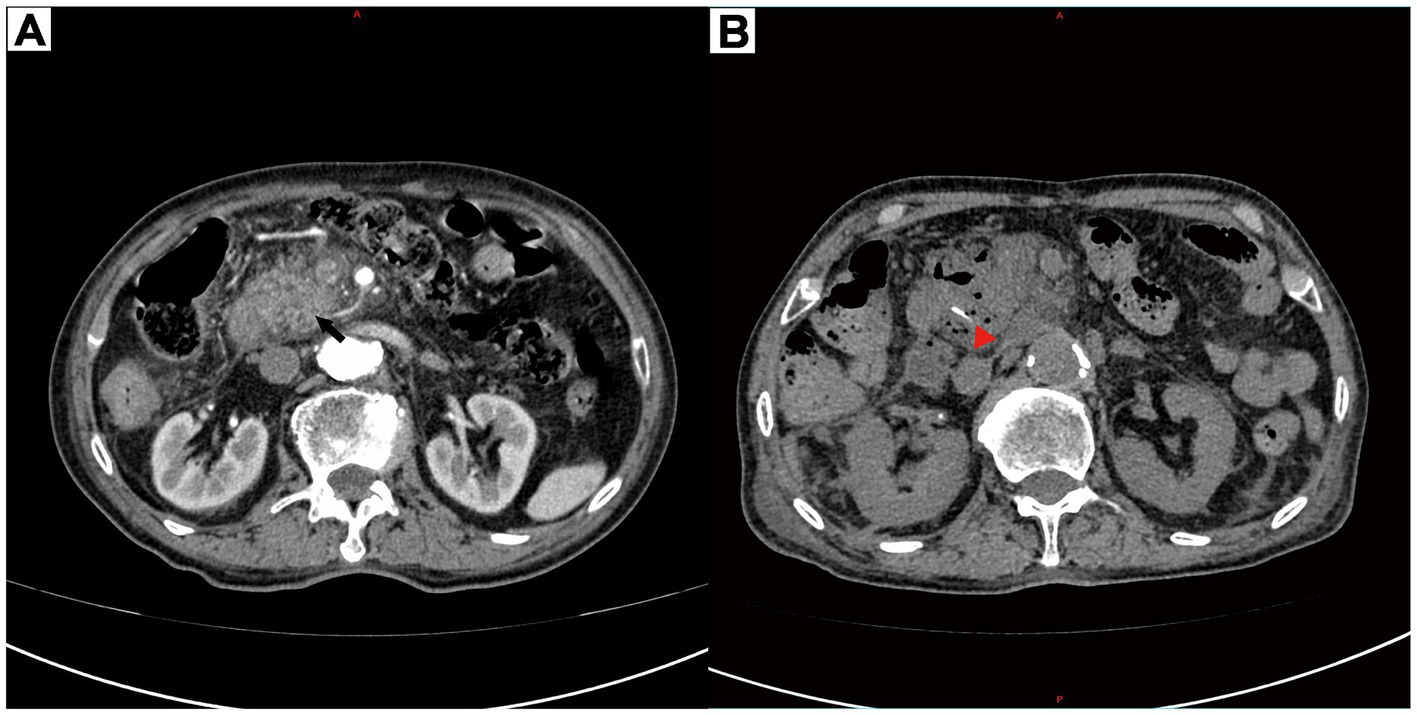

An 85-year-old man presented with 3 days of severe epigastric pain, nausea, and fever (38.3 °C). The abdominal pain was of a severe degree, not self-relieving. The patient has hypertension and Meniere’s disease, as well as a history of cerebral infarction. He denied alcohol consumption or gallstone history but had undergone a Billroth II gastrojejunostomy for a gastric ulcer more than 40 years ago. Physical examination revealed fever up to 38.3 °C, with pressure and rebound tenderness on palpation of the upper abdomen. Laboratory findings revealed elevated leukocytosis (13.8 × 109/L) and CRP (119.4 mg/L), but normal serum amylase (58 U/L) (Table 1). Abdominal contrast-enhanced computed tomography (CECT) demonstrated pancreatic head edema and peripancreatic exudation (Figure 1A). No biliary obstruction was observed. Consequently, the diagnosis of acute pancreatitis was made. After admission to the hospital, the patient was fasted, given gastrointestinal decompression, acid suppression with proton pump inhibitors, inhibition of pancreatic secretion with growth inhibitors, anti-infection with antibiotics, and started on intravenous fluids.

Figure 1

(A) Contrast-enhanced computed tomography showed fullness of the head of the pancreas, peripheral oozing, and blurring of the surrounding fat space (black arrow). (B) Contrast-enhanced computed tomography showed a localized hyperdense shadow (red triangle) in the head-duodenal region of the pancreas with a long diameter of approximately 21 mm and a fixed morphology.

However, after several days of treatment, initial conservative therapy (fasting, antibiotics, octreotide) failed to alleviate the symptoms. Although the abdominal pain persisted, the blood and urine amylase levels were still not high. Repeat CECT revealed a linear hyperdensity shadow in the pancreatic head-duodenal region (Figure 1B). The patient then underwent an emergency laparotomy and was classified as ASA IIIE according to the American Society of Anesthesiologists (ASA) Physical Status Classification System. Emergency surgery revealed infection around the pancreatic head and duodenum. Despite abscess drainage, no foreign body was initially detected. Intraoperative endoscopy was subsequently performed, and a 2.1 cm long fish bone was identified in the gastric pouch, which was successfully removed with foreign body forceps. The patient experienced intraoperative tachycardia and hemodynamic instability, requiring postoperative intensive care with endotracheal intubation for further life support. Two weeks later, with stable vital signs and no surgical complications, he made a full recovery and was successfully discharged from the hospital. Figure 2 shows the timeline of clinical presentation and treatment during hospitalization.